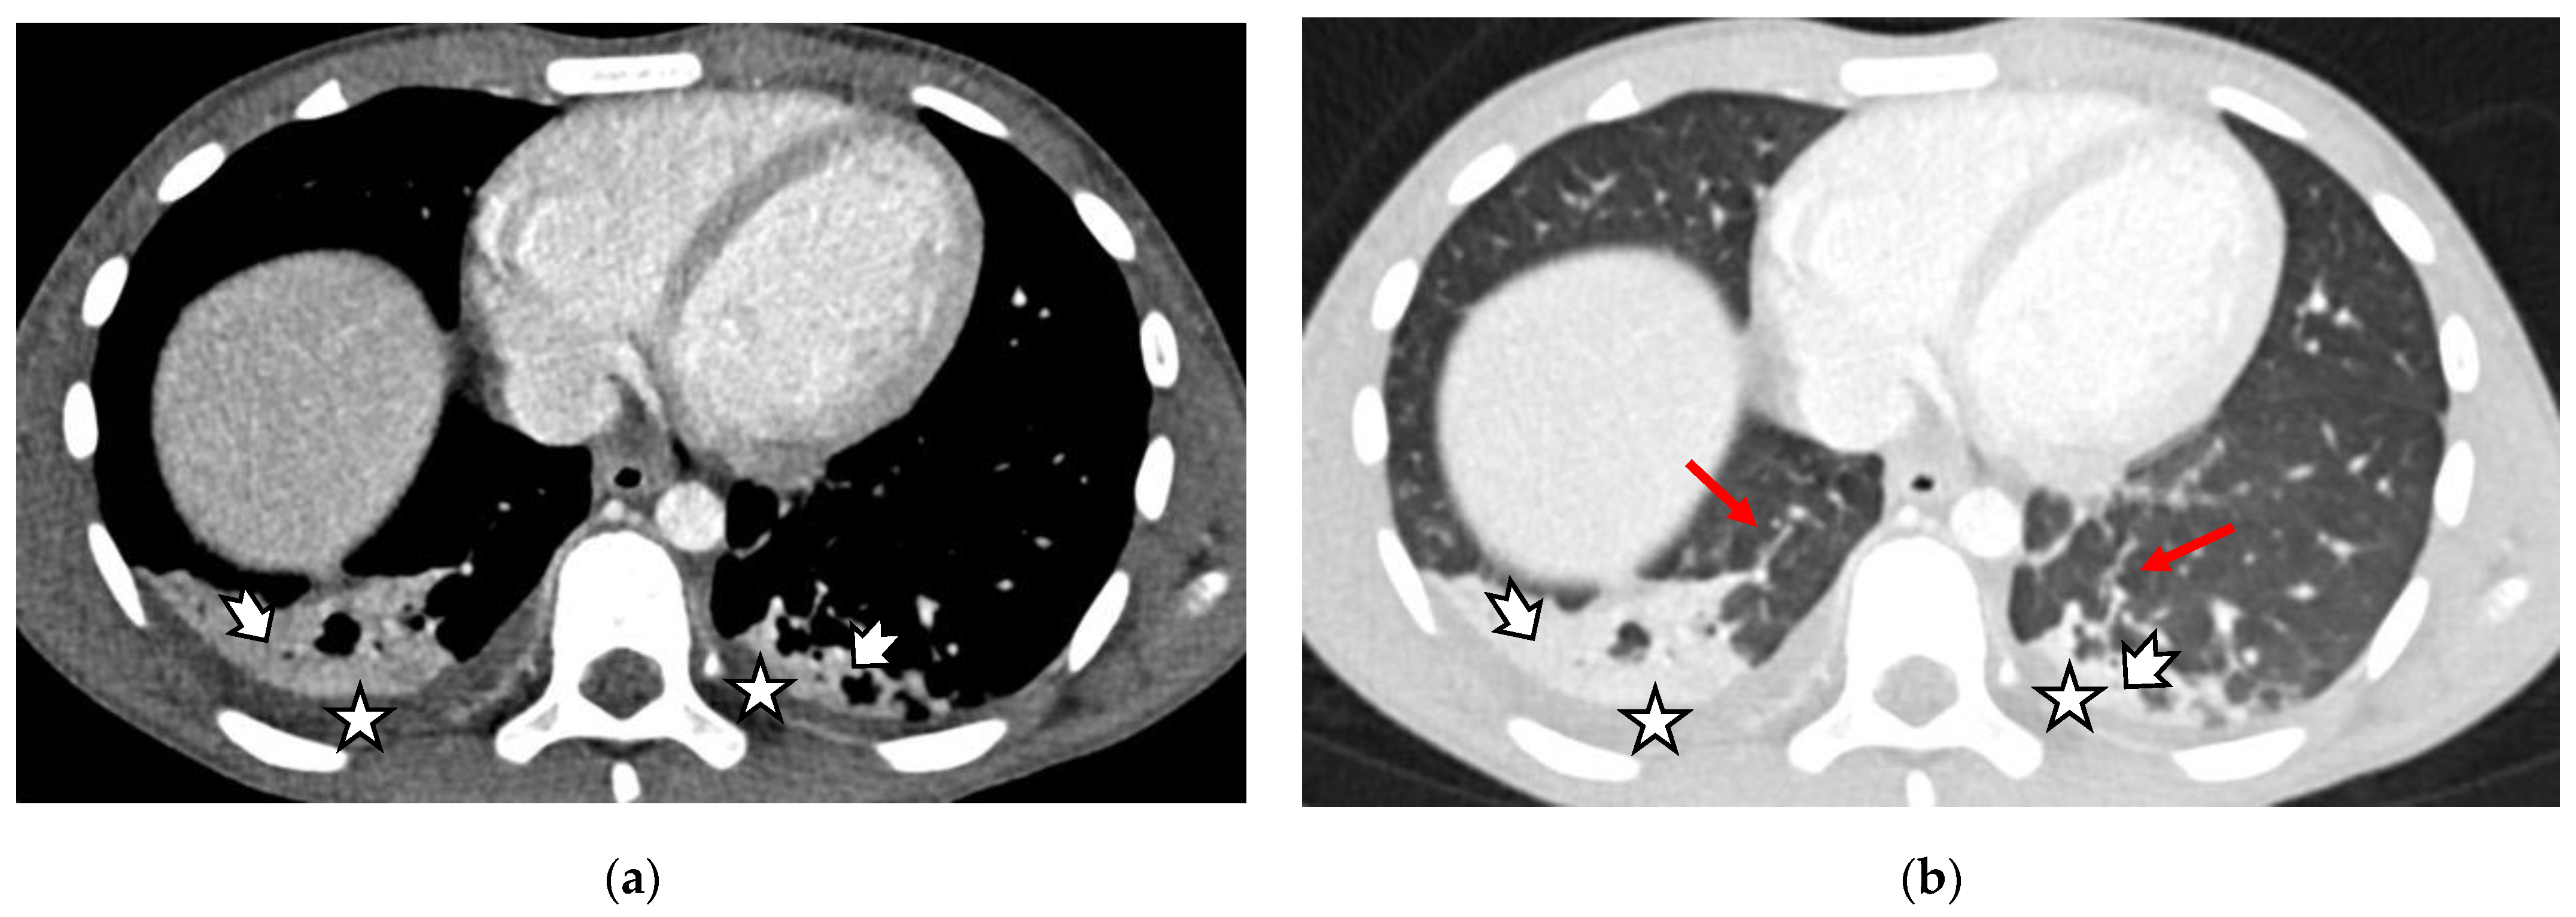

- Cardiovascular abnormalities including cardiomegaly (Figure 1c) and signs of pericarditis, myocarditis, and pericardial effusion.

| Chest CT scan findings, N 22 | CT ground glass | 12 | 54.5% | 23.5% |

| Crazy paving pattern | 1 | 4.5% | 2.0% | |

| Subsegmental atelectasis | 5 | 22.7% | 9.8% | |

| Posterior basal consolidation | 16 | 72.7% | 31.4% | |

| Air bronchogram | 3 | 13.6% | 5.9% | |

| Pleural effusion | 14 | 63.6% | 27.5% | |

| Pericardial effusion | 4 | 18.2% | 7.8% | |

| Cervical lymphadenitis | 10 | 45.5% | 19.6% | |

| Mediastinal lymphadenitis | 4 | 18.2% | 7.8% | |

| Axillar lymphadenitis | 3 | 13.6% | 5.9% | |

| Thymic enhancement | 5 | 22.7% | 9.8% | |